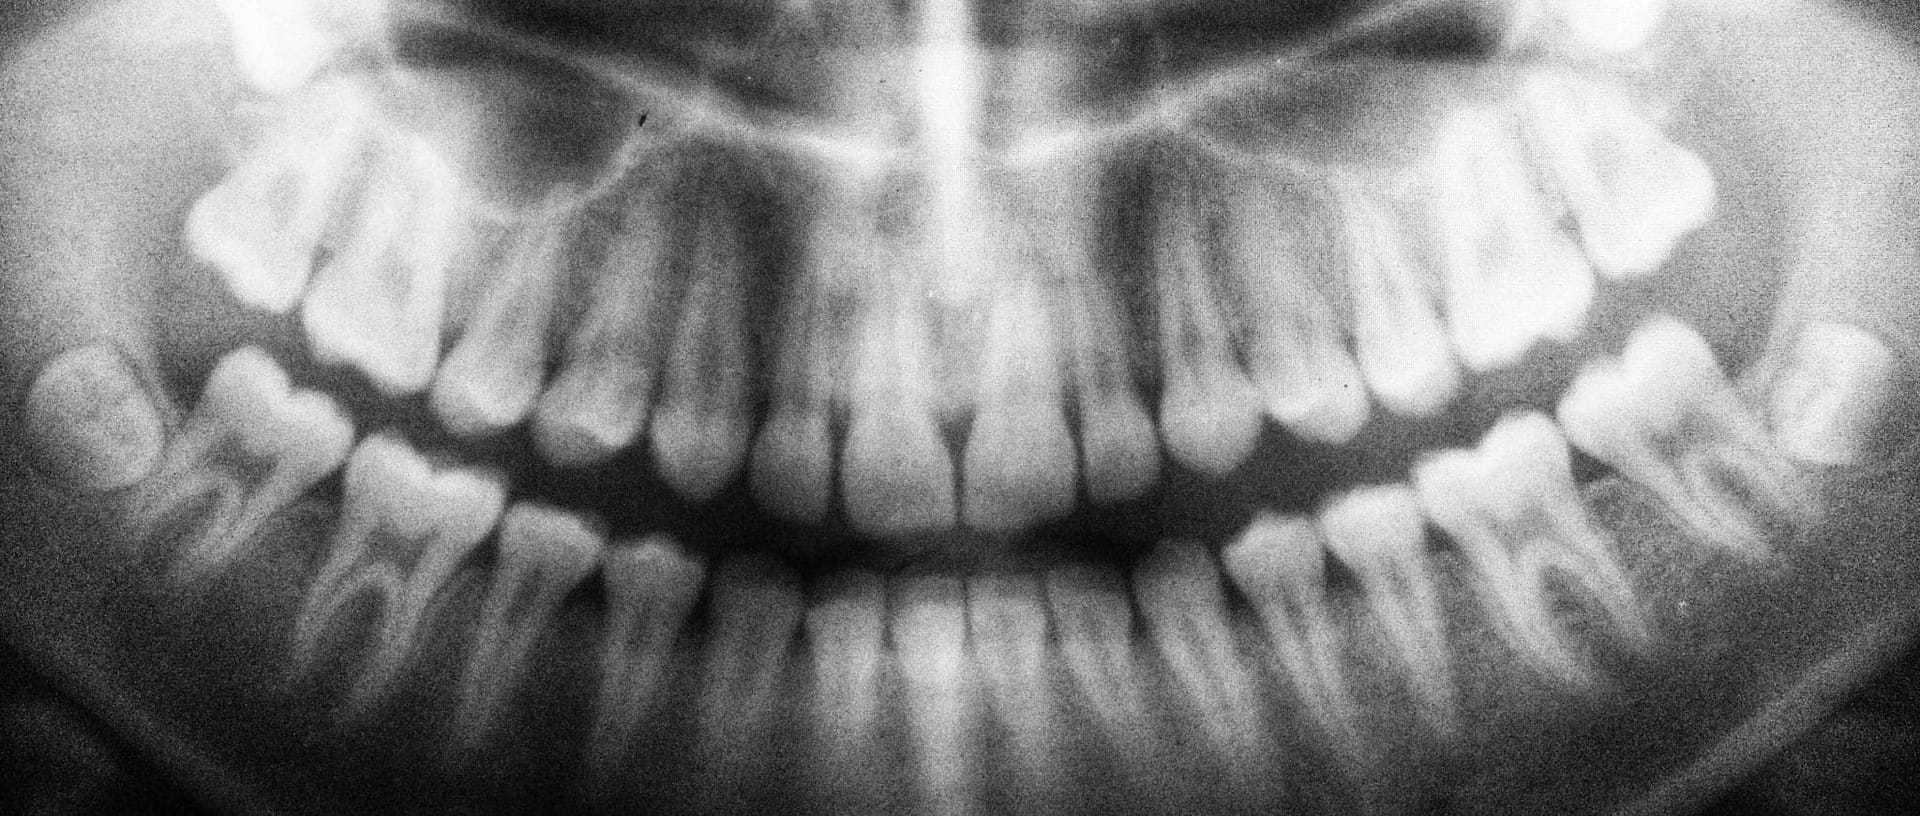

She exclaimed that there was absolutely nothing wrong with my teeth and that a filling would be completely unnecessary. When I had gone to Mint Dentistry, their dentist had lied about cavities to me.